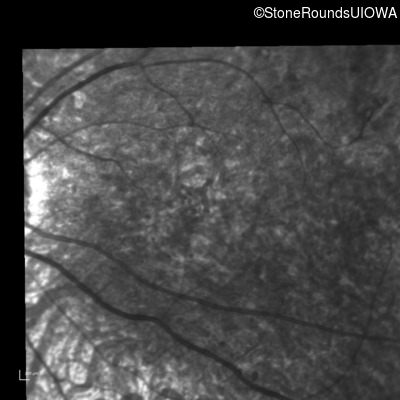

Blue Autofluorescence - Right - 10/400 sc

Exemplar

Blue Autofluorescence - Left - 10/300 sc